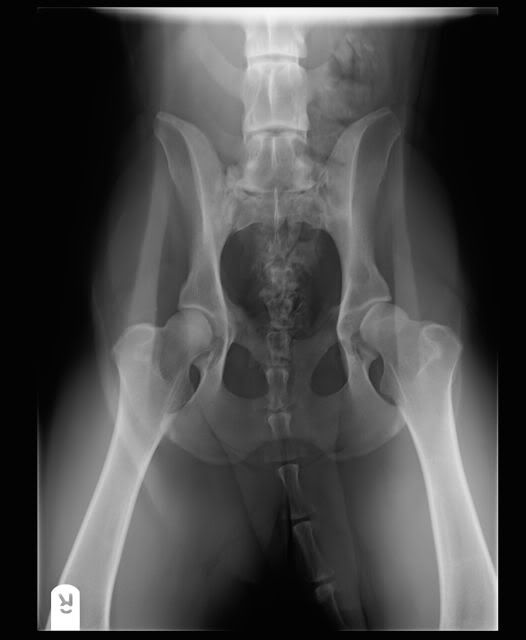

Marieta schreef:Hier haar heupjes, daar zal het niet aan liggen geloof ik![]()

Rechts is niet zo goed als links...

En de kant die er minder goed uitziet is de linkse kant;o) Ik probeer het ff hoe het zit met dat voer en hoe het met haar oortjes gaat. Dat heb ik met een week gezien. Dan is de reactie er meestal al wel (voorheen teminste wel).